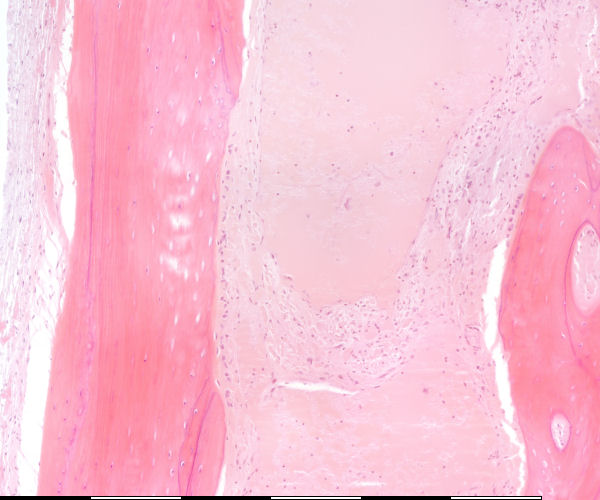

back Immature bone